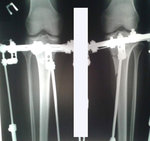

У пациентки плоскостопие 2-ой степени.

26 лет.

Дата операции 08.10.2015г.